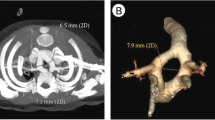

Type 5—right-sided, s-shaped, transverse

The AD lies on a transverse plane, between the proximal right PA and the descending aorta. The first part of the AD runs to the right, anteriorly to the trachea. The second part bends posteriorly to join the descending aorta on the right-anterior corner of the spine (Fig. 5a). This view resembles a capital letter “H” (Fig. 5b) or an inverted lowercase “h” (Fig. 5c), depending on whether the left PA is included in the section plane or not. The long-axis view of the AA allows a useful cross-check in these cases. In RAA and right AD of this type, two vessels will be seen in cross section behind the ascending aorta instead of only the right PA seen in normal anatomy (Suppl. Fig. IIa, b).

Three-vessel and trachea view of a 28-week gestational-age fetus with right AA and type 5 AD. The gray-scale image (a) shows how the right pulmonary artery runs anteriorly to the trachea and gives origin to a right-sided AD which joins the descending aorta at the anterior-right corner of the spine and leaves the trachea to the left. Posteriorly to the main pulmonary artery, the left pulmonary artery is seen. In contrast to the normal mirror-image “V” type, the corresponding color flow image resembles that of the letter “H” (b) or an inverted “h” (c) when the left pulmonary artery is not included in the section. d Cartoon of the same section shown in a-c. This case was not associated with intracardiac anomalies. AAO ascending aorta, AD arterial duct, DAO descending aorta, L left, MPA main pulmonary artery, LPA left pulmonary artery, R right, SVC superior vena cava, T trachea

Type 5

RAA and right AD of type 5 was observed in 9 cases (9%) including 3 cases with situs solitus, no associated CHD, and mirror-image branching of the AA. These cases were characterized by an uneventful postnatal course. Only 1 case, where partial agenesis of the corpus callosum was detected prenatally, developed mental retardation. However, in 3/3 cases, asymptomatic hypoplasia of the left PA was found on postnatal echocardiography. The other 6 cases had various forms of CHD (p = 0.4642) but none of these were associated with POO.

Recent studies described prenatal diagnosis of RAA and right “H” shaped AD (type 5) [24,25,26]. All except one case with double outlet right ventricle had normal intracardiac anatomy and confluent pulmonary arteries, and were benign with no vascular ring. Some authors [26, 27] emphasized how this can be overlooked if examiners miss that both arches are right of the trachea, and because the V-sign is maintained. In our experience, different ultrasound characteristics make it difficult to confuse with the mirror-image type. In our series, 3 cases with situs solitus and no associated CHD had smooth postnatal course, confirming the condition’s benignity. However, postnatal assessment revealed asymptomatic hypoplasia of left pulmonary artery in all cases. This association has been reported in a postnatal series [23]. Of note, with this AD type, postnatal complications may occur that require specific therapeutic approaches above those needed with normally-positioned AD [28,29,30,31].